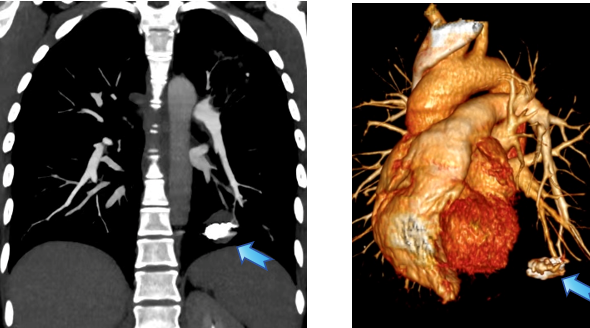

经过超选择性插管,完整显示动脉瘤轮廓与供血

在手术室和麻醉科的支持下,瑞金医院血管微创介入治疗团队为王女士实施介入手术:由王忠敏主任医师主刀、王子寅副主任及单群刚主治医师担任助手,从股静脉穿刺建立通道,在影像引导下将导管逐级送入左肺下叶病变分支,完成超选择性插管,造影清晰显示动脉瘤轮廓与供血。确认定位后,于瘤腔内精准释放多枚解脱弹簧圈,阻断瘤内血流。复查造影未见残余充盈,提示出血风险已被当场解除。整个过程不开胸、不切肺,体表仅有一个微小穿刺点。

术后CTA复查:动脉瘤得到了精确且完全栓塞

术后第二天肺动脉CTA复查显示:动脉瘤被完全“封堵”,局部血流切断。王女士恢复平稳,未再出现咯血,随后顺利出院。她感慨道,感觉自己全好了!